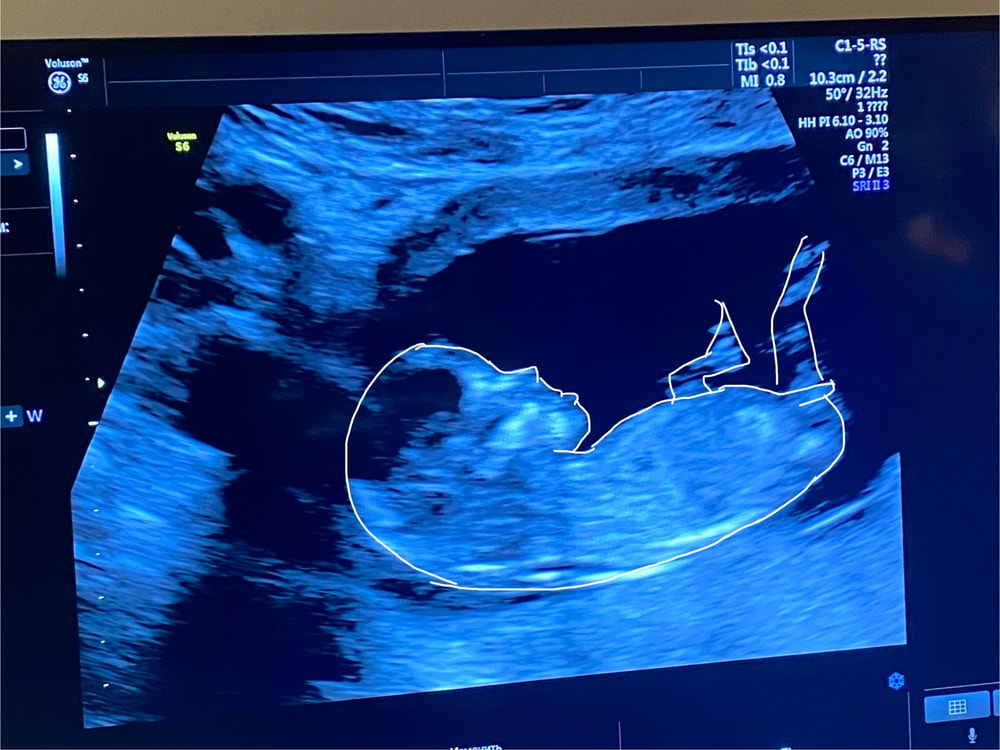

Я была на УЗИ в 12+3, у меня тоже был отлично виден этот шарик - половой бугорок. Как мне сказали, на этом сроке он одинаковый и у мальчиков, и у девочек, но у мальчиков имеет характерный наклон вверх, а у девочек расположен горизонтально и параллельно туловищу.

Вопрос к вам)) у кого на первом скрининге видели половой бугорок и говорили ли на какой пол похож? И совпало ли в итоге потом? Мне предположили девочку, интересно потом проверить данную теорию.